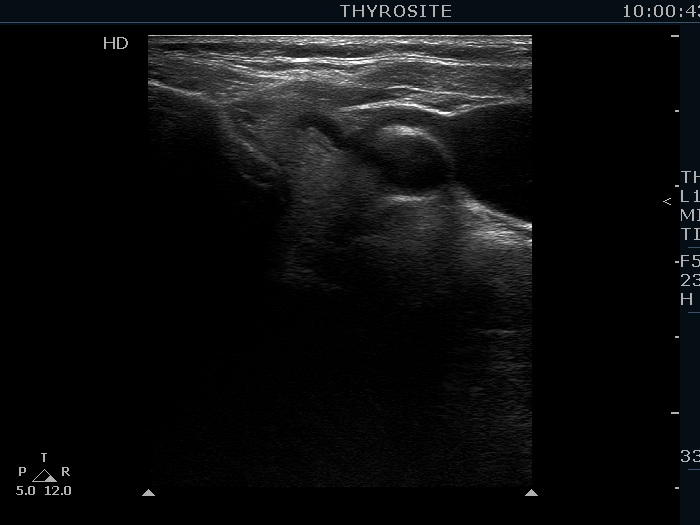

Intranodular hyperechogenic figures - case 928 (ultrasonographic picture 5)

Left lobe, longitudinal view. There is a small echonormal lesion.